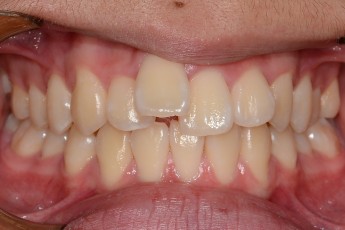

BEFORE & AFTER

- 돌출입교정